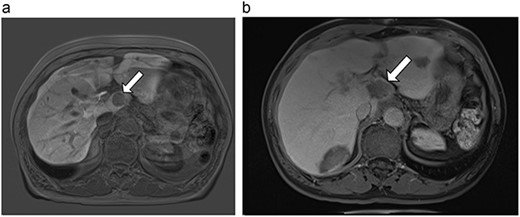

(a) Pre-ablation MRI demonstrates 6 mm lesion in caudate lobe of liver. (b) Post-ablation MRI (18 days postoperatively) demonstrates 40.4 mm complete ablation site in caudate lobe of liver.

| 1 (3a,b) | 61, F | Colon adenocarcinoma | 6-month FOLFOX | 1 | Laparoscopic microwave ablation | 6 | 40.4 | 34.4 | 10 | No |